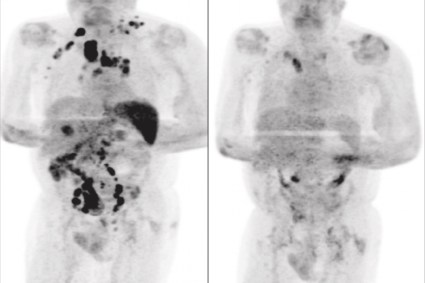

Exame de tomografia revelou a remissão generalizada do linfoma

Quatro meses depois, os médicos afirmaram que o inchaço dos nódulos havia diminuído. Um exame de tomografia revelou a remissão generalizada do linfoma.